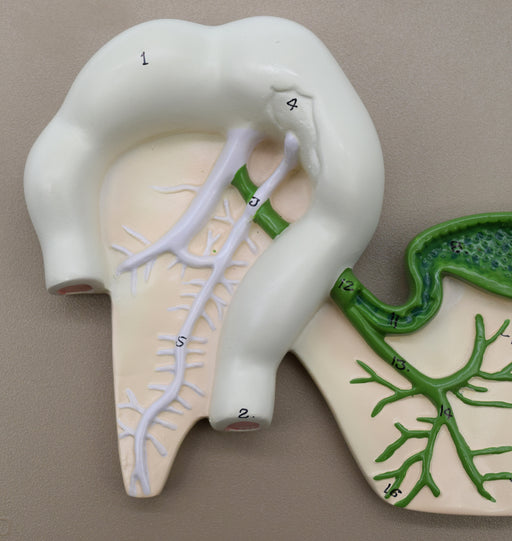

Human Pancreatic Duct Model, Three Dimensional, with Hand Painted Details - Mounted on Base, 10" x 7" - Eisco Labs

Model depicts human pancreatic duct. Mounted on a 10" X 7" base . Entire model stands 2.25" tall. Numbered with English Key Card. Hand painted Mod...

View full detailsAM0330 -